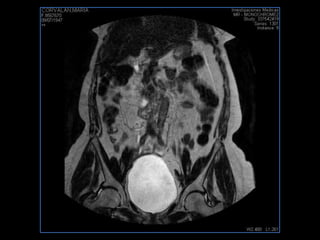

PROTOCOLO pelvis SAG T2, Y FAT SAT (FINOS) AXIAL T1  AX FAT SAT CON   GADOLINIO :  AX T1 Y COR T1 SAT: NO  FASE: RL THK: 3MM  COIL:  GAP: (FACTOR 1.4) 1MM FOV: 40 CM NEX:2 SINCRONIZACION RESPIRATORIA EN 3 O 4 CICLOS ALE

resonancia de abdomen